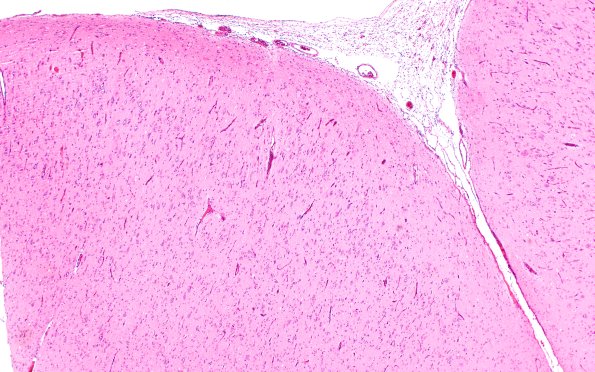

Washington University Experience | DEVELOPMENTAL MALFORMATIONS | Tuberous Sclerosis | 16B2 Tuber (Case 16) 4X H&E

16B2-5 This cortical tuber is shown at several magnifications. The normal cortical pattern is replaced by disorganized dyslaminate cortex characterized by large dysmorphic neurons in superficial cortical layers and numerous, occasionally binucleate, astrocytes and ballooned cells with indeterminate origin with neuronal nuclei and glassy “glial” cytoplasm. (H&E)